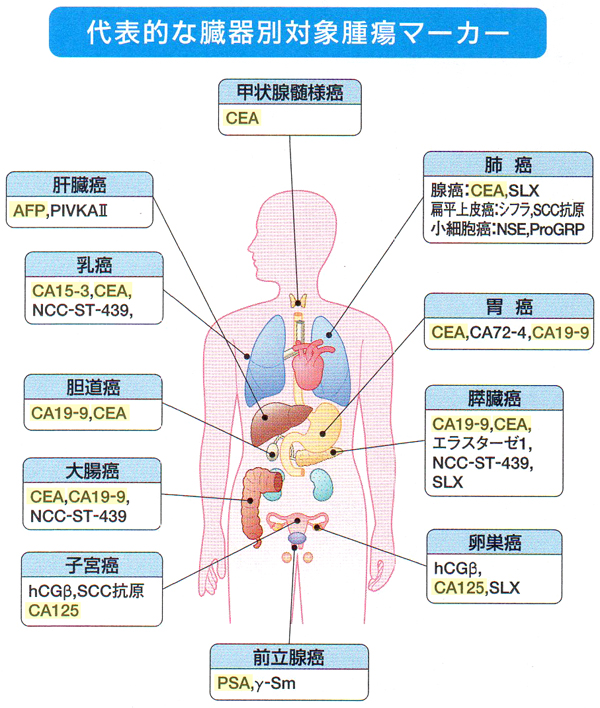

◆腫瘍マーカー検査 1項目1,500円(税抜)~

腫瘍マーカーとは、癌細胞の指標となる特殊な物質の総称で、癌早期発見のためのスクリーニング(ふるい分け)検査として用います。この検査によって、癌細胞の性質や、どの部位の癌かを推測することができます。全ての癌をカバーする腫瘍マーカーはありませんので、発見しにくい癌の腫瘍マーカーをお得なセットにしました。もちろん、ご希望の項目のみでも可能ですので、お気軽にお問い合わせください。

・CEA ・・・・・・・・胃がん、大腸がん、肺がん、乳がん、胆道がん

・AFP ・・・・・・・・肝臓がん

・CA19-9 ・・・・・・ 膵臓がん、胆道がん、胃がん、大腸がん

・PSA [男性] ・・・・ 前立腺がん

・CA125 [女性] ・・・ 卵巣がん、子宮がん

・CA13-5 [女性] ・・・乳がん

検査方法・・・採血したものを検査します。

お勧めする方・・・喫煙歴が長い方や、家族に癌を罹った人がいる方